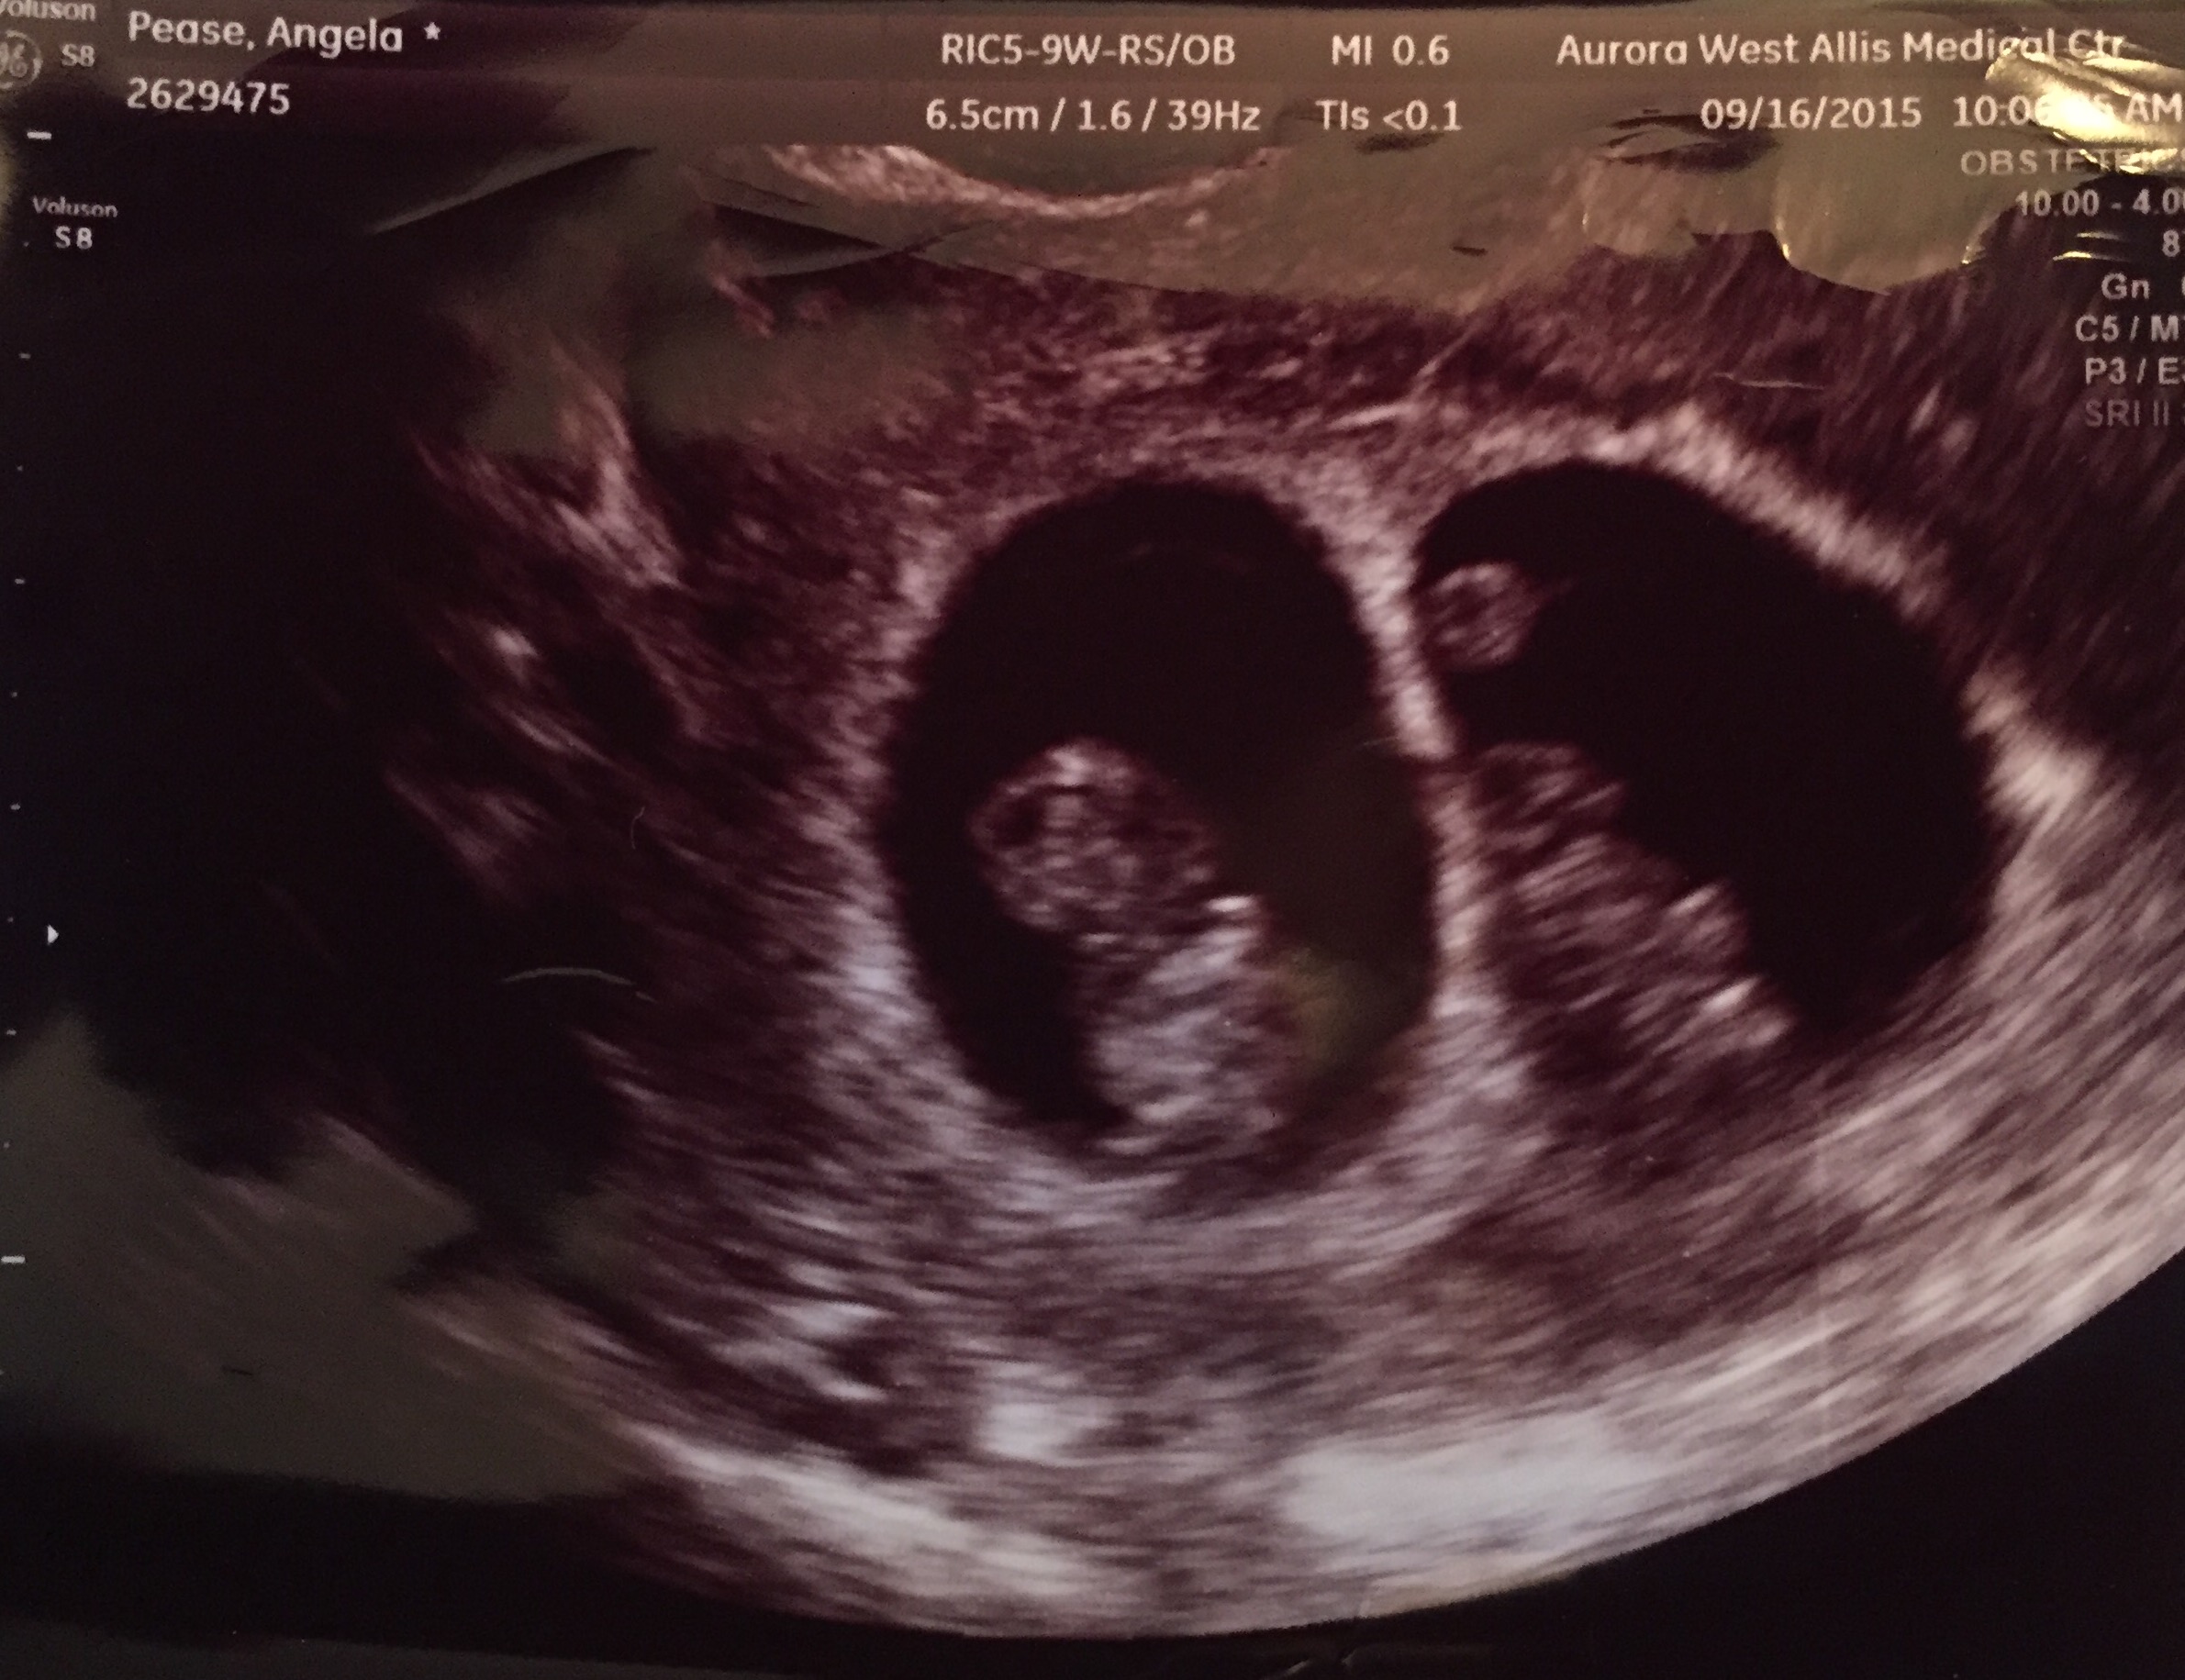

Ricky and I had our 11 week ultrasound yesterday and the twins are doing great! They were moving so much the doctor couldn't get them in the save picture. We graduated from the fertility clinic and I got to stop all my hormone supplements!!! YAY! We have our first OB appointment at 14 weeks on October 21st.